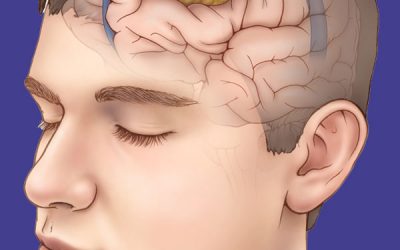

سردردهای خطرناک؛ چه زمانی نشانه سکته یا تومور مغزی هستند؟

سردردهایی که قبل از سکته یا تومور مغزی ظاهر میشوند سردرد یکی از شایعترین شکایتهای پزشکی است، اما آیا همه سردردها بیخطر هستند؟ در برخی